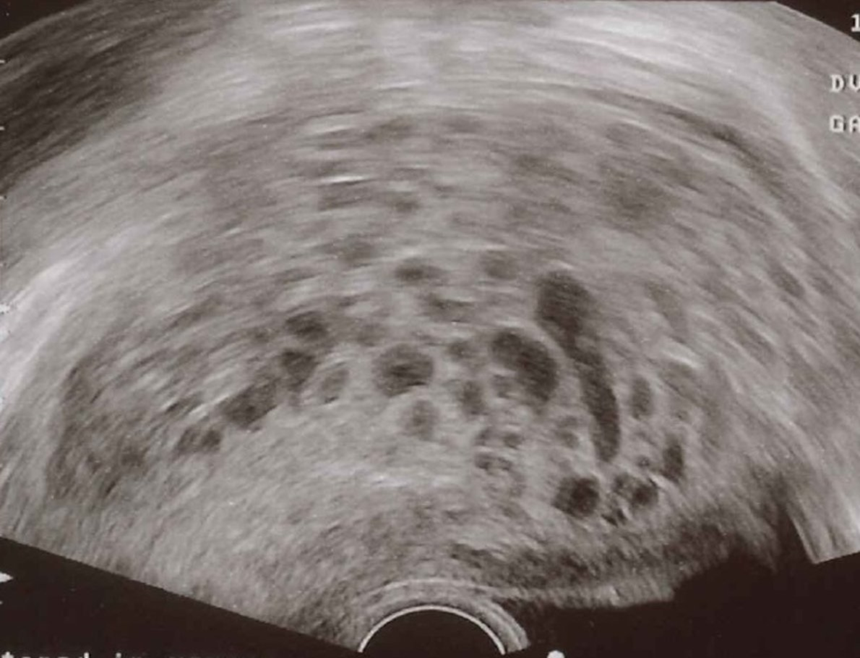

Hydatidiform mole Ultrasound pelvis (transvaginal)

of pregnant patient with abnormally elevated β-hCG level

There is no intrauterine gestation. An intrauterine mass contains multiple cystic spaces .This vesicular appearance seen in a molar pregnancy has been described as a “snowstorm pattern”.